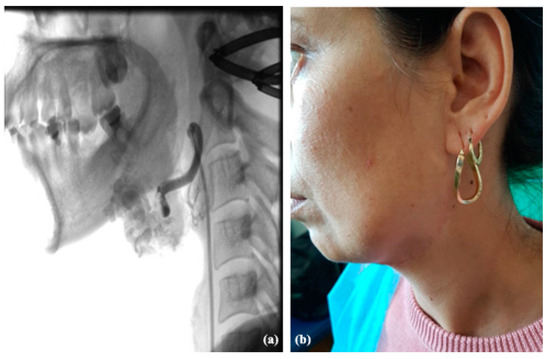

3.3. Arteriovenous Malformations

3.3.1. Clinical Data

3.3.2. Diagnosis

3.3.3. Therapy